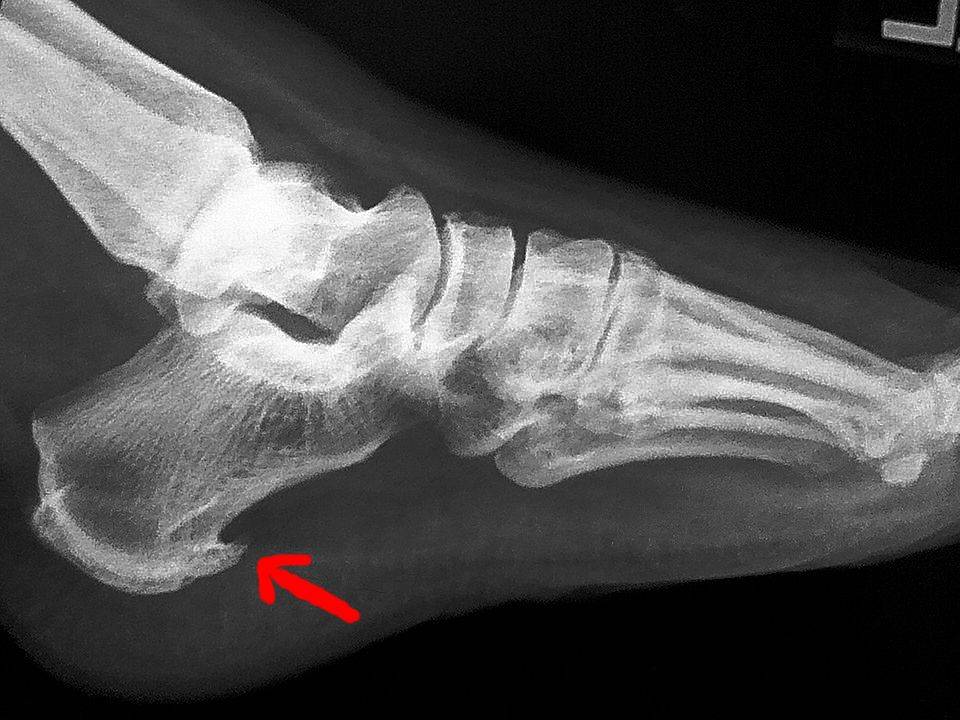

1. 🦴 踵骨棘とは?

踵骨棘とは、かかとの骨(踵骨)にトゲのような骨の突起ができる状態です。 この骨棘自体が痛みの原因になることもありますが、多くの場合は足底筋膜炎が関係しています。

足底筋膜が硬くなったり炎症を起こしたりすると、骨が引っ張られて骨棘が形成されやすくなります。